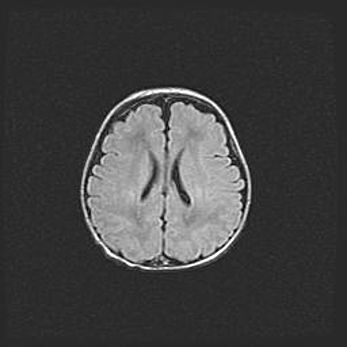

Сообщающаяся гидроцефалия. Кистозная энцефаломаляция головного мозга.

Возраст: 3 месяца 4 дня

Вес: 3100 г

Пол: женский

Окружность головы: 34 см

Срок гестации: 31 неделя

Кистозная энцефаломаляция головного мозга - одна из форм поражения головного мозга в детском возрасте. Характеризуется возникновением множественных и распространённых кист в коре, белом веществе и подкорковых образованиях головного мозга у плодов, новорождённых и детей раннего возраста. Развитие кистозной энцефаломаляции связано с внутриутробной асфиксией и гипотонией, родовой травмой, тромбозом синусов, пороками развития сосудов, инфекциями, сепсисом и другими причинами. Наиболее значимые инфекционные агенты: вирусы простого герпеса, цитомегалии, краснухи, токсоплазмы, энтеробактерии, золотистый стафилококк и другие.